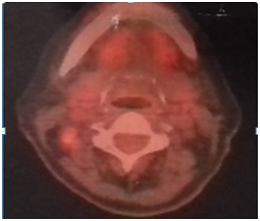

The patient underwent radical node dissection (45 lymph nodes), who’s biopsy revealed reactive histiocytosis. FNB of the thyroid lesion (Figure 2) depicted metastatic infiltration from the same ovarian carcinoma. After this diagnosis, a right lobe lobectomy was performed. FNA of the liver, under ultrasound guidance, indicated fatty liver and fibrosis with no signs of malignancy. Thyroid biopsy confirmed the diagnosis of malignant metastatic lesion 2x1, 5cm by the ovarian carcinoma (Figure 3,4). The 7 local lymph nodes were negative for infiltration from the neoplasm. The patient started chemotherapy with CDDP/Docetaxel with adjuvant intends, after 4 weeks, mainly to treat the potential mediastinal metastatic lymphadenopathy (we have no biopsy from this site at present).

Figure 3 Thyroid infiltration by high grade serous carcinoma with classic cytological figures. (H & E X 200).